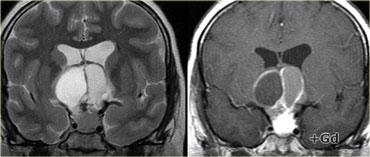

U Tuyến Yên Đại Tuyến (Macroadenoma)

Theo định nghĩa, u tuyến yên đại tuyến (macroadenoma) là các u tuyến có kích thước trên 10mm.

Chúng thường là các tổn thương đặc, mềm, thường có các vùng hoại tử hoặc xuất huyết khi kích thước tăng lên.

Khi phát triển, u trước tiên làm giãn rộng hố yên (sella turcica) rồi sau đó phát triển lên trên.

Trong ví dụ về u tuyến yên đại tuyến này, có sự lan rộng lên vùng trên yên (suprasellar) với sự đẩy lên và chèn ép giao thoa thị giác.

Do là các khối u mềm, chúng thường bị thắt lại tại màng hoành yên (diaphragma sellae), tạo nên hình ảnh ‘người tuyết’ đặc trưng.

Đây là một đặc điểm giúp phân biệt u tuyến yên đại tuyến với u màng não (meningioma).

Một đặc điểm khác có thể giúp phân biệt là sự giãn rộng của hố yên – điều này thường chỉ xảy ra với u tuyến yên đại tuyến có nguồn gốc từ trong hố yên.

Bên trái là một ví dụ khác về u tuyến yên đại tuyến.

Tổn thương bắt đầu từ hố yên, vốn đã bị giãn rộng, và lan rộng vào bể dịch não tủy trên yên (suprasellar cistern).

Lưu ý hình ảnh ‘người tuyết’ kinh điển được tạo ra do sự thắt nghẽn bởi màng hoành yên.

Chú ý mức dịch-máu (blood-fluid level), cho thấy có xuất huyết.

Trên các hình ảnh chuỗi xung T2W bên phải, có thể thấy các lá màng hoành bị đẩy lên trên bởi khối u đại tuyến này, vốn bắt đầu từ hố yên và đang phát triển lên trên.

Một tổn thương có nguồn gốc từ phía trên hố yên và phát triển xuống dưới sẽ đẩy các lá màng hoành theo hướng ngược lại (điều này có thể thấy trong trường hợp u màng não chẳng hạn).